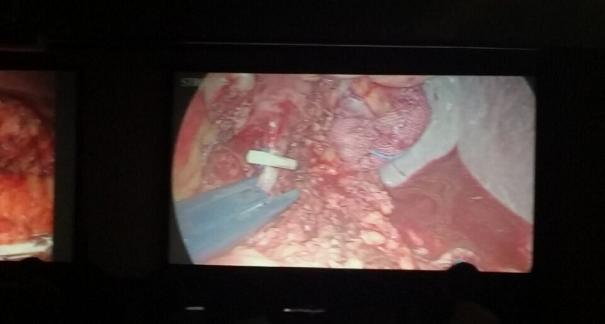

2015年10月23-25日,河北省醫(yī)學(xué)會肝膽外科學(xué)術(shù)年會在河北省石家莊市頤園賓館隆重召開。本次學(xué)術(shù)會議河北省醫(yī)學(xué)會特邀了北京301總院的胡明根教授、天津第一中心醫(yī)院的張雅敏教授、山西醫(yī)大醫(yī)院的趙浩亮、河北醫(yī)科大學(xué)第二醫(yī)院劉建華教授等國內(nèi)知名專家參會。參加會議的醫(yī)院達(dá)100余家,近300名肝膽外科的臨床專家和一線醫(yī)生們親臨會場,在此進(jìn)行廣泛的學(xué)術(shù)交流。25號全天會議安排了五臺手術(shù)視頻演示,全體參會人員進(jìn)行觀摩,并實(shí)時提問,進(jìn)行手術(shù)交流。演示手術(shù)包括腹腔鏡胰、十二指腸切除術(shù)、腹腔鏡左、右半肝切除術(shù)、腹腔鏡門脈高壓癥的治療、兩鏡或三鏡聯(lián)合膽石癥的治療、開腹胰、十二指腸切除術(shù)、手術(shù)演示中多次使用了我公司產(chǎn)品速豐(可吸收止血結(jié)扎夾),產(chǎn)品使用滿意度受到專家們的一致好評。